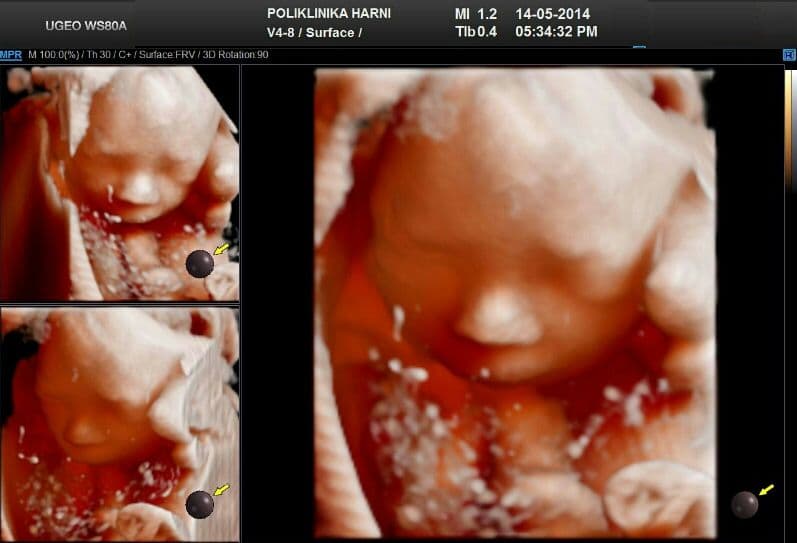

Uporabom 5D tehnologije, pored feto-realističnog prikaza kao jedne od najznačajnih karakteristika prikaza, u isto vrijeme je moguće sagledati ispitivani organ ili organski sustav iz različitih kutova, koji se vrlo često ne mogu dobiti standardnim ultrazvukom. Ovo se osobito korisnim pokazalo u procjeni središnjeg živčanog sustava u svjetlu epidemije Zika virusne infekcije, ali i kod sumnje na druge infekcije i abnormalnosti središnjeg živčanog sustava